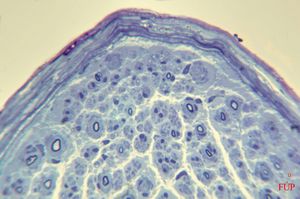

F,23y. | - n.suralis- hypertrophic demyelinizing neuropathy (onion bulbs)

F,23y. | - n.suralis- hypertrophic demyelinizing neuropathy (onion bulbs)